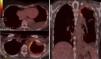

Presentamos el caso de una mujer de 60 años que fue remitida a nuestra unidad ambulatoria de patología pleural por derrame pleural izquierdo. Refería dolor torácico izquierdo de características pleuríticas de 8 semanas de evolución, tos seca y deterioro del estado general. En la exploración física destacaba una auscultación pulmonar caracterizada por hipofonesis basal izquierda. No tenía antecedentes de tabaquismo, trabajaba como ama de casa y ni ella ni su familia tenían exposición tóxica ambiental ni laboral, incluyendo al asbesto. Así mismo, su zona de residencia habitual no se encontraba cerca de industrias relacionadas con el asbesto u otras posibles fuentes del mismo. Había sido tratada 10 años antes de un carcinoma ductal infiltrante de mama mediante mastectomía, quimioterapia y radioterapia. En la analítica destacaba: VSG 90mm/h, PCR 42,9mg/l, fibrinógeno 656mg/dl y CA 15,3 44,1U/ml. La prueba de tuberculina fue negativa. Tras la realización de una toracocentesis diagnóstica el líquido cumplía características de exudado linfocitario, siendo el ADA de 21UI/l y la citología negativa para malignidad. La biopsia pleural con aguja de Abrams guiada por ecografía torácica obtuvo fragmentos de tejido pleural y musculoesquelético sin alteraciones patológicas. La tomografía por emisión de positrones-tomografía computarizada (PET-TC) mostraba hipercaptación en la pleura apical izquierda y en la zona subpleural basal izquierda con un SUV máximo de 6,8 y 3,8g/ml, respectivamente (fig. 1). Ante la ausencia de diagnóstico se llevó a cabo una punción aspiración con aguja fina transtorácica guiada por TC en la zona de mayor hipercaptación del PET-TC cuyo análisis citológico evidenció la presencia de proliferación mesotelial atípica. El diagnóstico final anatomopatológico se obtuvo mediante una biopsia pleural por videotoracoscopia tras obtener un fragmento de tejido compatible con mesotelioma maligno pleural de tipo epitelial.